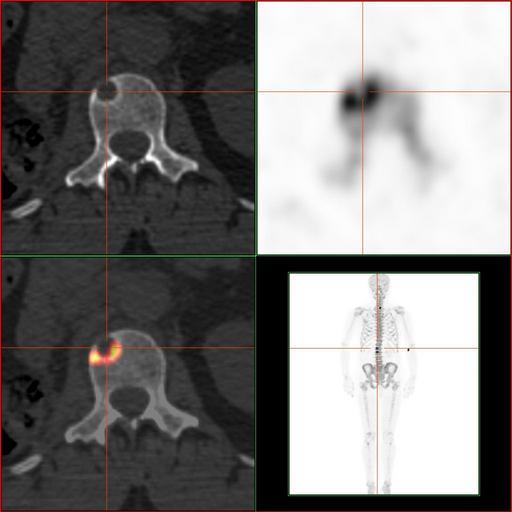

MAKE A MEME View Large Image RenalCancer-90MBq-F-18-Fluorid-PET-CT Vergleich.jpg en Sodium fluoride PET/CT Scan of a bone metastasis of kidney cancer; the PET scan shows the metabolic reaction of the bone de Natriumfluorid-PET/CT-Aufnahme einer Knochenmetastase eines ...

Keywords: RenalCancer-90MBq-F-18-Fluorid-PET-CT Vergleich.jpg en Sodium fluoride PET/CT Scan of a bone metastasis of kidney cancer; the PET scan shows the metabolic reaction of the bone de Natriumfluorid-PET/CT-Aufnahme einer Knochenmetastase eines Nierentumors Die PET-Aufnahme zeigt die metabolische Reaktion des Knochens own Hg6996 2011-03-16 Mit freundlicher Genehmigung Südwestdeutsches PET-Zentrum Stuttgart am Diakonie-Klinikum Cc-zero Positron emission tomography